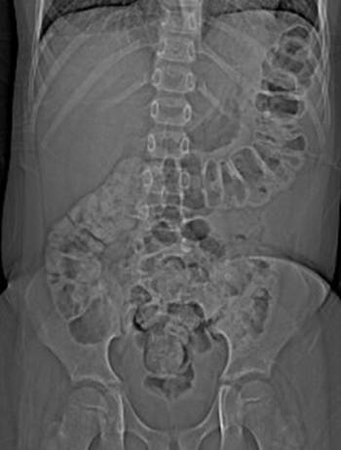

Radiografia abdominal de menino com dor abdominal aguda intensa, revelando fezes em todo o cólon e reto

Do acervo de Dr. KuoJen Tsao; usado com permissão